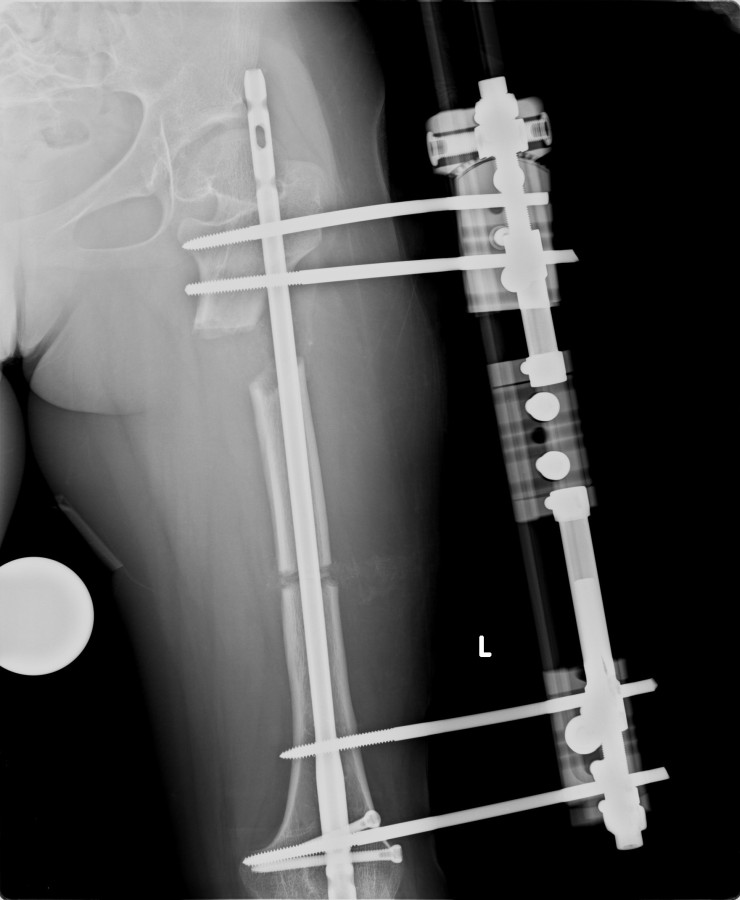

14 ve 16 yaşlar arasında her iki femurda toplam 10-12 cm boy uzatma her iki kalçanın fleksiyon deformitesinin düzeltilmesi (bu lomber hiperlordozu düzeltir) her iki kalçanın varus deformitesini düzeltme ortalama eksternal fiksasyon tedavi süresi = 10-12 ay

13-15 yaşlar arasında Her iki humerusu (kol) 8-12 cm boy uzatma Dirseklerin fleksiyon deformitesini düzeltme Ortalama eksternal fiksasyon tedavi süresi = 6-8 ay Alt uzuvların iki uzatması arasında üst uzuvlar uzatılarak alt uzuvların dinlenmesi sağlanmış olur. Cihaz çıkartıldıktan sonra en erken ikinci uzatmaya başlama süresi 6 aydır. Bilateral femoral uzatmalarda uzatma fazı sırasında hastanın yürümesi mümkün değildir. Ayakta durmaya sadece hasta transferi sırasında izin verilir. Uzatma fazında ambulasyona sadece tekerlekli sandalye ile izin verilir. Konsolidasyon fazında ise tedrici olarak daha fazla yük verilmesine ve cihazın çıkmasına yakın serbest yürümeye izin verilir. Bilateral tibial uzatmalarda ilk günden itibaren yürüteç veya koltuk değneği ile hastanın yük vermesine izin verilir. Uzun gezintiler tekerlekli sandalye ile yapılmalıdır. Bilateral humeral uzatmalarda hemen hemen hiçbir aktivite kısıtlaması yoktur. Uzatma süresince her iki haftada bir yapılan takiplerde kantitatif duyusal sinir testleri doktor tarafından yapılmalıdır. Bu gelişmekte olan sinir sorunlarını klinik olarak ortaya çıkmadan yakalamaya izin verir. Femoral ve humeral uzatmalarda çok nadir görülmesine rağmen tedavi edilmedikleri durumda düşük ayağa (ayağı yukarı çeken kasları innerve eden sinirin felci) neden olabilirler. Eğer erken tespit edilir ve uzatmanın hızı azaltılırsa, sinir problemi genellikle kendiliğinden düzelir ve uzatmaya düşük hızda devam edilir. Uzatmada yavaşlamaya rağmen sinir problemi devam ederse sinirin cerrahi olarak gevşetilmesi gerekir. Bu işlem 1cm’ lik bir kesi ile yapılabilen ve hastanede bir gece kalmayı gerektiren küçük bir işlemdir. Bu ameliyat el bileğinde sinir sıkışması (karpal tünel sendromu) için yapılana benzerdir.